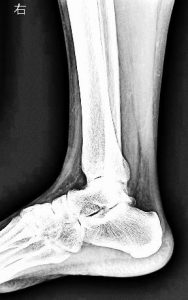

一般撮影部門

検査を目的とする部位にX線を照射して、身体を通過した情報から画像を作り、疾患や骨折の有無などを調べる検査です。一般的に“レントゲン撮影”、“X線撮影”、“単純撮影”などと言われています。簡便かつ迅速に画像が提供できる特長があり、最初の診断に用いられることが多い検査です。

2020年3月に、FPD(Flat Panel Detector:平面検出器)を導入し、被ばく線量を抑え短時間できれい(高精細)な画像を提供できるようになりました。

撮影室2(胸部・腹部・脊椎・四肢等):RADspeedPro(島津製作所)

撮影室3(胸部・腹部・脊椎・四肢等):MRAD-A80S RADREX(キヤノンメディカル)

撮影室4(胸部・腹部・脊椎・四肢等):RADspeedPro(島津製作所)